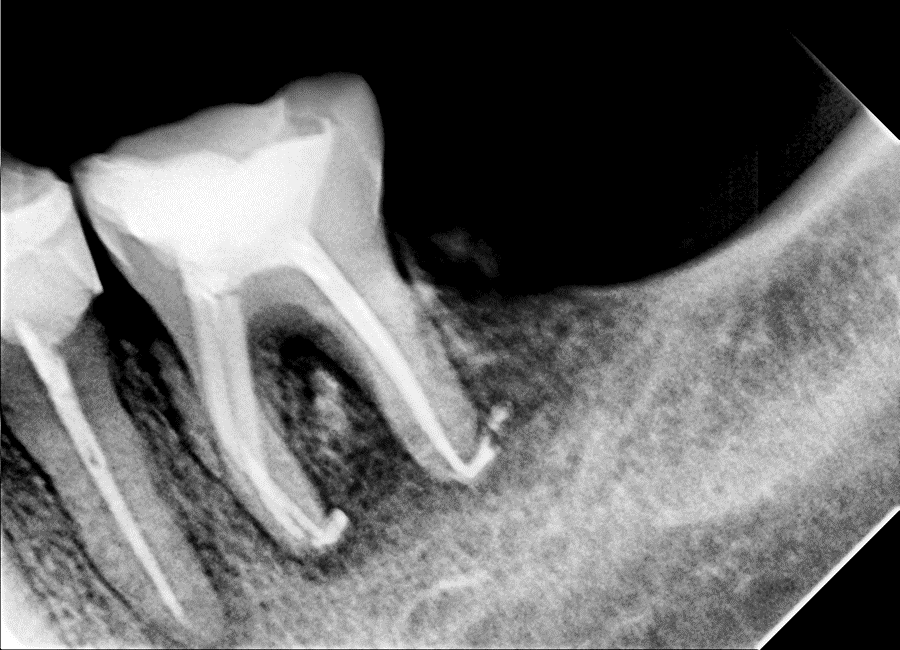

At 7 months, radiographs showed substantial periapical and furcation bone regeneration. Radiopaque remnants (“sealer puff”) were visible but asymptomatic. Clinically, no pain or mobility; probing depths reduced.

Figure 3. 7-month follow-up radiograph showing significant bone regeneration and radiopaque sealer remnants.

The rapid healing observed aligns with previous reports on hydraulic calcium silicate sealers encouraging mineralized tissue formation via high pH and calcium ion release. The visible sealer residue is common in single-cone techniques with bioceramics and does not indicate pathology. Compared to other sealers, nRoot offers high radiopacity, ease of use, resin-free formulation, and good biocompatibility. Limitations include being a single case report, lack of histologic confirmation, and moderate follow-up duration. Further controlled trials comparing healing rates would be valuable.

Figure 3